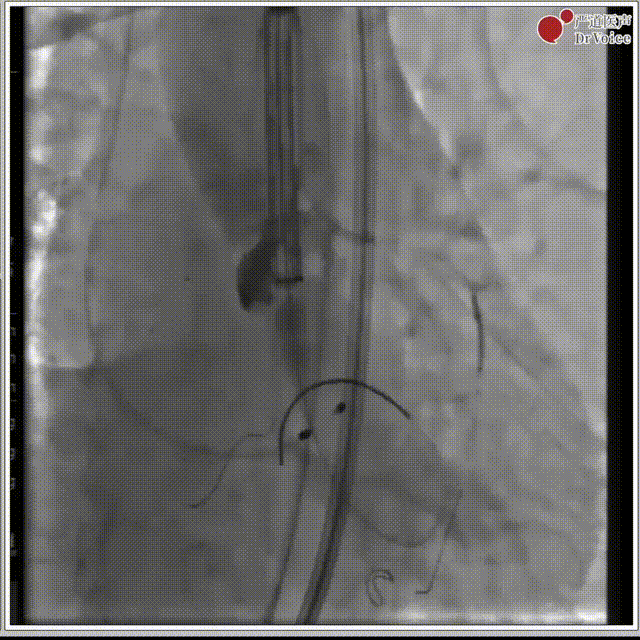

1. 冠脉造影。

冠脉造影图片1

冠脉造影图片2

2. 冠脉保护,左冠预埋支架。

冠脉保护后造影